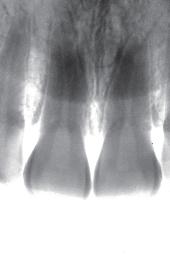

Remarkably, the patient’s chief concern was the gingival recession on the left maxillary lateral, not the mesial caries. (Fig. 8) Fortunately, the patient’s oral hygiene was relatively good, and restoring the MLB decay was

straightforward (BeautiBond (Fig. 7) and Beautifil Flow Plus X, both from Shofu USA, San Marcos CA). The steps for the esthetic rectification of the buccal recession are:

1. Gently micro-abrade the receded area and the apical enamel to remove food debris and plaque. The nozzle of the abrader should be angled incisally to prevent gingival irritation and bleeding. Rinse thoroughly and lightly air dry, leaving the surface slightly moist (although the degree of moistness is not critical).

2. Apply BeautiBond, a 7th generation dental adhesive, and leave for 10 seconds. Thoroughly air dry the adhesive (very critical). Light cure with the Fusion 5 Curing Light (Dentlight, Plano TX), offering deep cure of composite resins within 3 seconds with a uniform 4000 mW/cm2 output. (Fig, 7A)

3. Select the appropriate Beautifil II Gingiva shade (Light Pink and Violet for this patient) and apply to the receded area to restore the buccal dimension and contour of the original soft tissue. Light cure. It is important to leave a small (0.25-0.50mm) gap between the apical margin of the restorative and the free gingival margin. (Fig. 9) This space prevents gingival irritation, is easily maintainable by the patient, and is generally not visible even with closeup photographs. (All photography done with the Shofu EyeSpecial camera, (Fig. 10) Shofu USA, San Marcos CA.)